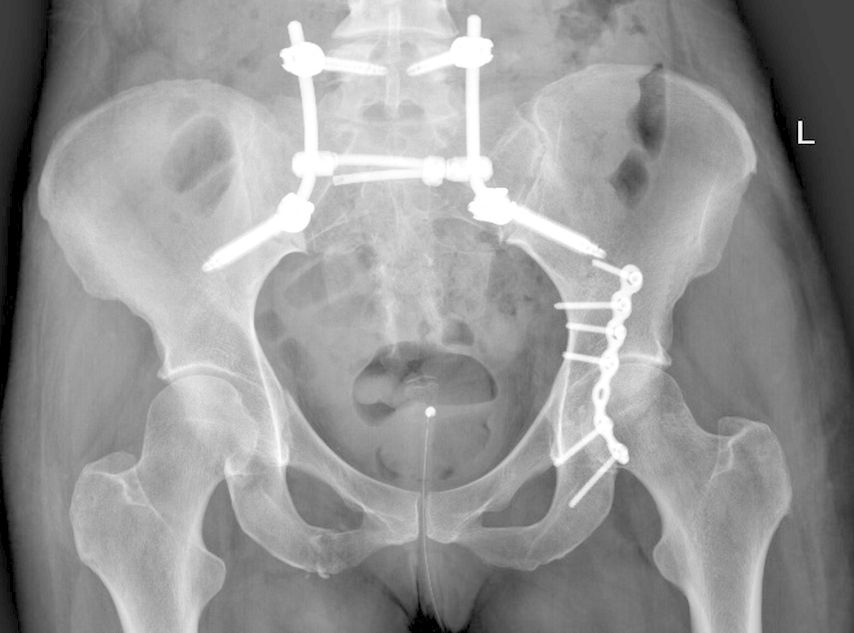

Abb. 2: Beckenübersicht einer 48-jährigen Patientin mit lumbopelviner Stabilisierung und Acetabulumplattenosteosynthese nach Sturz aus grosser Höhe mit lumbopelviner Dissoziation und mehrfragmentärer transforamineller Frakturkomponente, oberer und unterer Schambeinastfraktur rechts und Acetabulumfraktur links